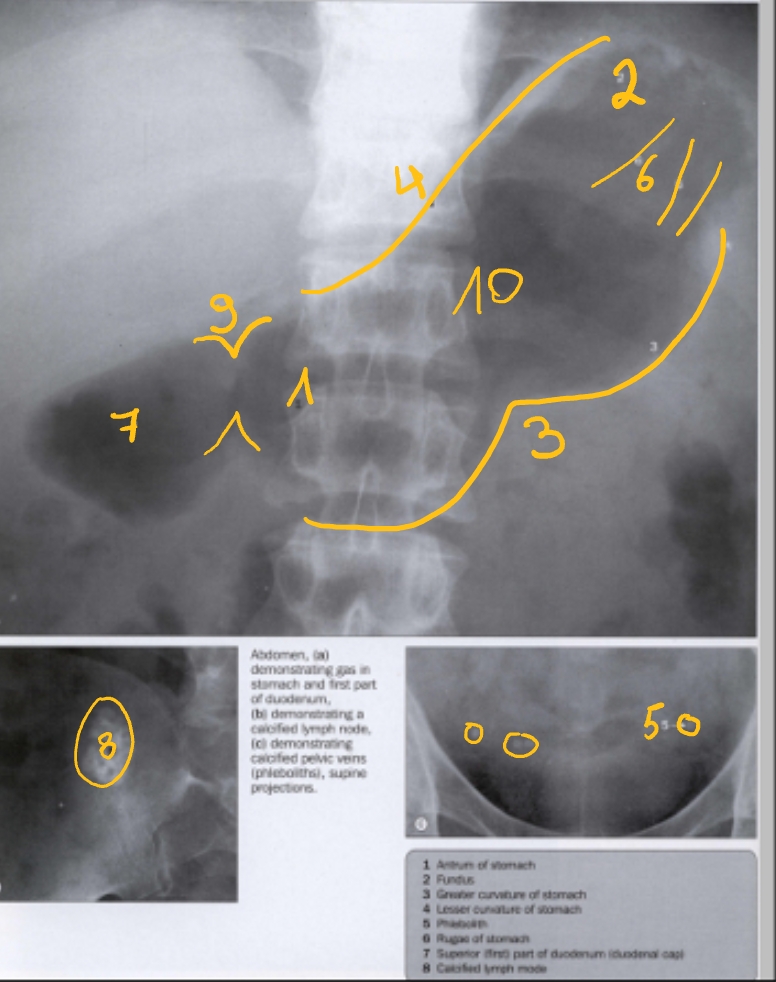

antrum

f

curvatura major

curvatura minor

flebolieten

→ verkalking van venen (geeft trombus)

rugae (maagplooien)

duodenum (bulbus)

verkalkte lymfeklier

→ door bacterie van koemelk (bij rechtstreeks drinken)

m. pylorus (inkeping)

corpus maag

(rechter hypochondrium)

galblaas

FOTO 1: dubbelcontrast (want veel lucht in maag)

FOTO 2: enkelcontrast (want weinig lucht in maag)

bulbus duodeni

(op moment dat die samentrekt)

pars descendens duodeni

pars transversa duodeni

pars ascendens duodeni

m. pylorus

(constante, geen peristaltiek)

fundus

corpus